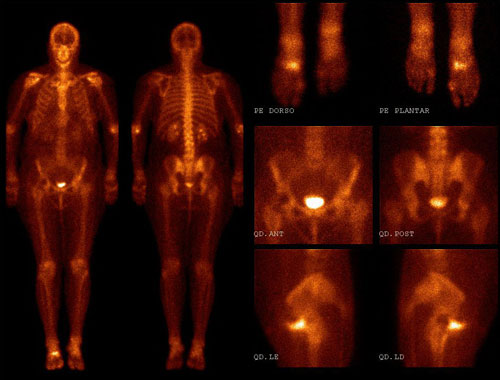

Internação para Cintilografia

Na Prodimagem, pacientes com câncer de tireoide em tratamento com iodo terapia contam com um espaço de internação seguro, acolhedor e preparado para cada etapa do cuidado. Nossa missão é oferecer diagnóstico preciso aliado a conforto e humanização.